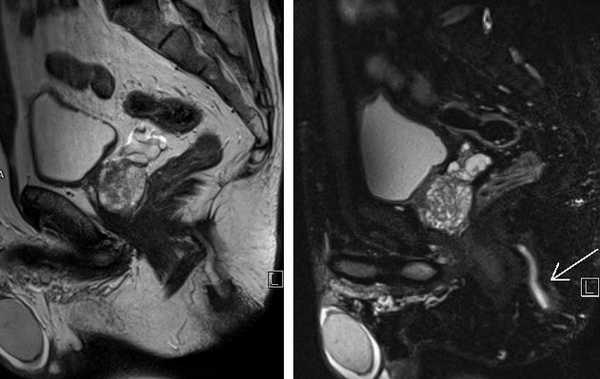

МРТ малого таза в сагиттальной плоскости. МР-признаки анального транссфинктерного свища (линейной формы, стрелка). Наружное отверстие расположено на коже перианальной области на расстоянии 32 мм от анодермальной линии.